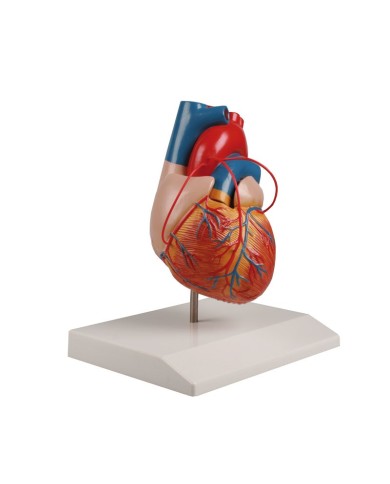

Fra i modelli di base segnaliamo il modello di cuore classico in due parti, in cui le due metà del cuore sono tenute insieme da potenti magneti.

Inoltre nella categoria sono presenti anche i modellini anatomici di cuore con bypass e con sistema di conduzione, fino ai modelli anatomici comparativi di patologie del cuore.

Per una migliore comprensione delle strutture anatomiche del cuore sono stati realizzati anche dei modelli anatomici di cuore ingrandito, si va dai piccoli ingrandimenti fino ai modelli di cuore per la formazione in aula, come il modello anatomico di cuore gigante prodotto da 3B Scientific: un modello di cuore ingrandito di ben otto volte.